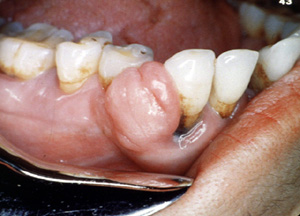

Este fibromaperiférico se proyecta desde la encía y se muestra enrojecido.

Parece un granuloma.